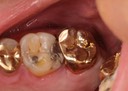

Mark Chun #13,14,15 pre-op

Mark Chun #13,14,15 amalgam removal

Mark Chun #13,14,15 prep